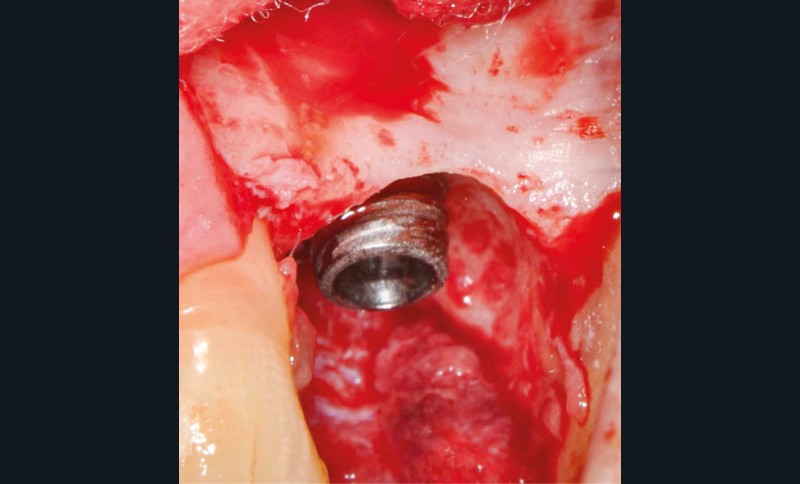

Chez cette patiente, le traitement de la péri-implantite a été réalisé à l’aide d’une technique de régénération osseuse guidée péri-implantaire, dont l’indication a été principalement motivée par la morphologie du défaut osseux. Au-delà de la maîtrise du geste chirurgical, le bon résultat obtenu à trois ans est intimement lié à sa coopération en termes de suivi et de contrôle de plaque.